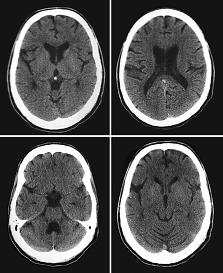

Головной мозг, орбиты, кости основания и свода

черепа

Для обнаружения первичных и метастатических

опухолей головного мозга КТ обладает широкими возможностями при их величине

свыше 7-8 мм. Критической зоной является стволовая часть головного мозга,

замкнутая в костное кольцо и неизменно перекрываемая артефактами. Опухоли

головного мозга характеризуются патологической зоной измененной плотности

определенной формы, с признаками объемного воздействия на окружающие структуры,

со сдавлением прилежащих полостей, с активным накоплением контрастного вещества

при внутривенном контрастировании. Некоторым первичным опухолям присуща

кистозная структура, с заполнением жидкостью (плотность не совпадает с

плотностью ликвора). Часто степень злокачественности выявленного

новообразования удается оценить только при гистологическом исследовании после

операции. Метастазы чаще всего окружены широкой зоной перифокального отека.

КТ головного мозга КТ глазниц